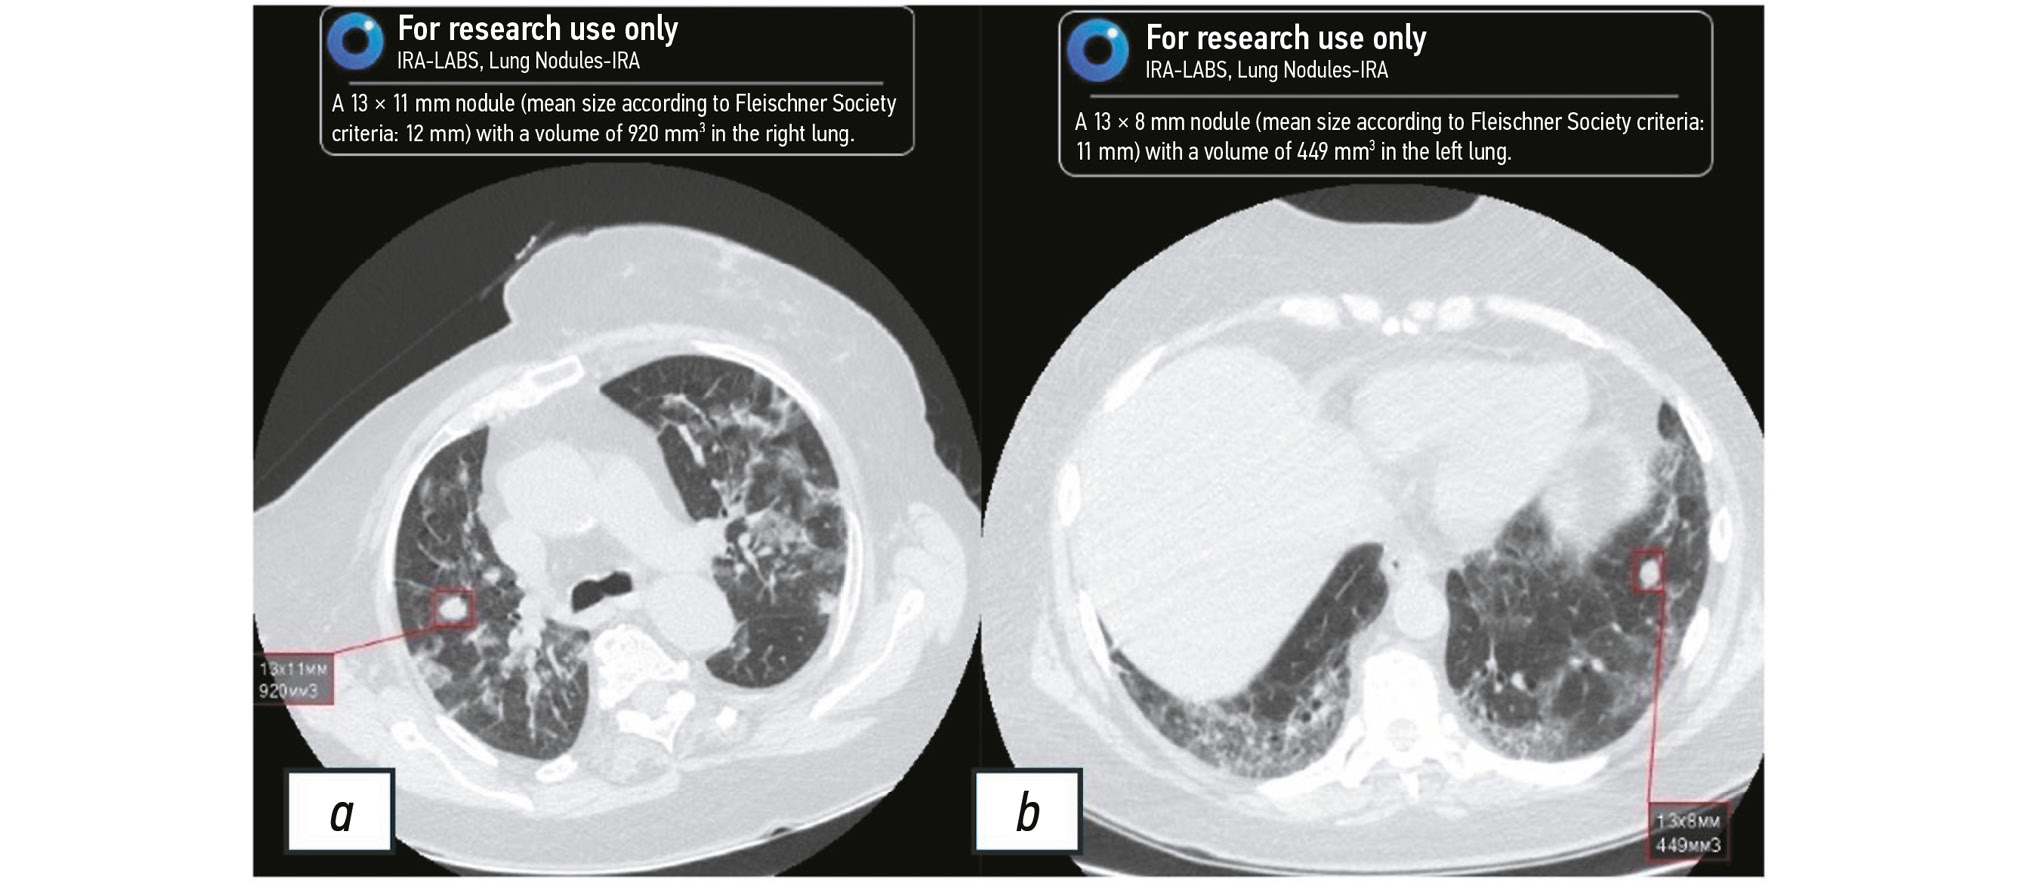

Fig. 3 and Fig. 4 illustrate the AI algorithm findings.

Fig. 3. Left lung nodule detected by artificial intelligence. The detected nodule is marked by the red square. Image with a high probability of lung cancer.

Fig. 4. Nodules in the right (a) and left (b) lungs detected by artificial intelligence. The detected nodules are marked by the red square. Images with inconclusive signs of lung cancer.